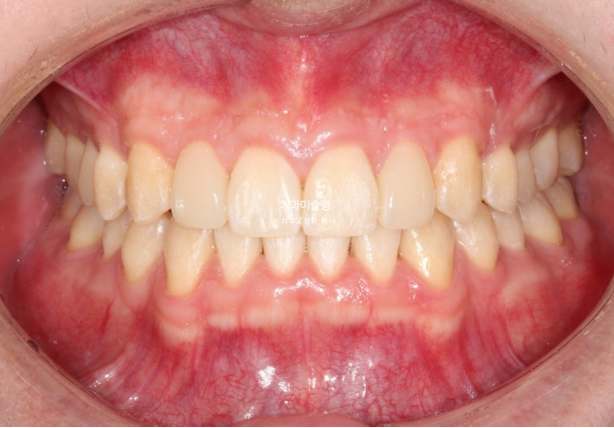

가위교합은 해결이 되었지만 아직 어금니 교합이 긴밀하지 않습니다.

배열은 완벽합니다.

중심선 등을 좀 더 바로잡고자 재제작에 들어갑니다.

위 아래 중심선은 정확히 맞고

어금니 교합관계도 1급 입니다.